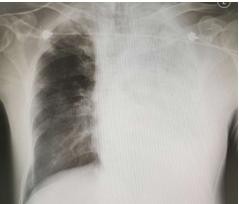

▲男子肺部變白。(圖/溫州新聞網)

不過初始的治療似乎並沒有有效阻止病情的進展,李大伯高熱不退,呼吸更為急促,幾乎喘不過氣,24小時不到,醫生再次為他復查胸片,結果讓人大吃一驚,左邊肺部基本全白。